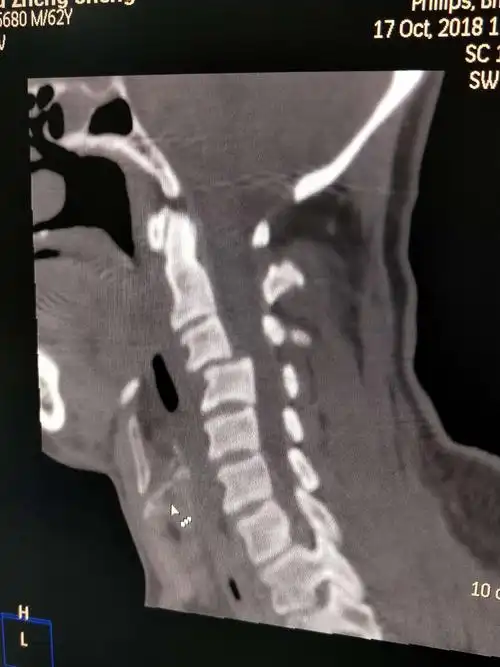

颈椎错位的诊治 安康市中心医院针灸科 杜宏斌

寰椎的位置和其与其它颈椎的位置没有明显的错位征.

颈椎骨折脱位 - 好大夫在线